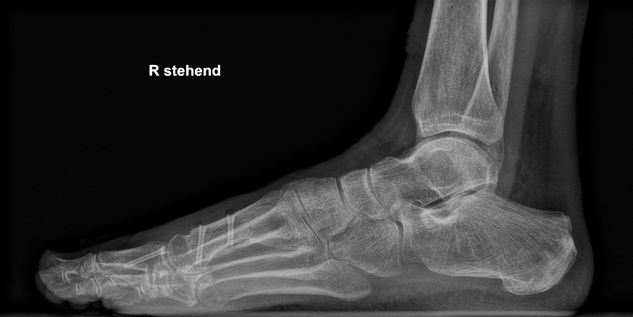

Implantate | Fuß

HBS 2 Resorb Mg und mm.CS

Nach über 100.000 erfolgreichen HBS- und HBS 2-Implantationen weltweit startet eine neue Ära mit der Erweiterung des Angebots um HBS 2 Resorb Mg Kompressionsschrauben. Diese innovative Schraube aus einer speziellen Magnesiumlegierung behält die bewährte HBS 2-Geometrie bei und ist nun zudem bioabsorbierbar. Auf diese Weise bleibt dem Patienten eine zweite Operation zur Metallentfernung erspart.

Magnesiumimplantate durchlaufen im Körper einen kontrollierten Abbauprozess, bei dem das Implantat in Knochen umgewandelt wird und Wasserstoffgas freigesetzt wird. Eine spezielle Oberflächenumwandlung verlangsamt die Korrosion des Implantats, wodurch die Abbaurate vermindert wird, was entscheidend für die Frakturheilung und die Integration des Implantats in das Knochengewebe ist.

Unser resorbierbares Schraubenportfolio, bestehend aus HBS 2 Resorb und mm.CS Implantaten unseres Kooperationspartners medical magnesium enthält kanülierte, kopflose Kompressionsschrauben in fünf verschiedenen Durchmessern. Dies ermöglicht den Einsatz in einem weiten Indikationsspektrum. Alle Schrauben sind selbstschneidend und können mit den bekannten und bewährten Operationstechniken eingesetzt werden. Lediglich das Kopfraumfräsen wird als zusätzlicher Operationsschritt ergänzt, um das Eindrehmoment beim Implantieren zu reduzieren.